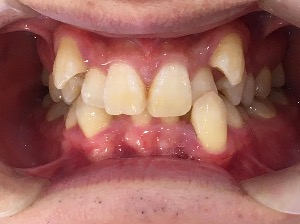

before

after

患者さんの年齢 20代 女性 症状 ガタガタを治したい 治療内容 マウスピース矯正治療 費用 90万(税抜) 治療期間・回数 治療期間2年、通院回数10回 メリット 笑顔が綺麗 デメリット・リスク 期間がかかることがある - マウスピース矯正